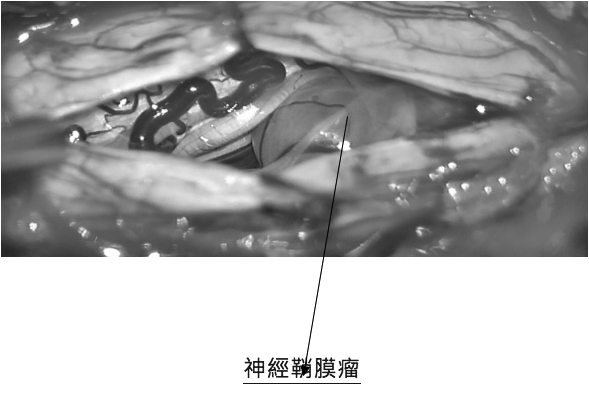

48歲李先生從國內到香港找醫生醫治他的雙腿痳痺及乏力症狀,他已在國內兩年間接受中西療法都不能把他的症狀改善。李先生兩年前只覺得腳踭痛,但慢慢發現腳步走路不穩及大腿肌肉無力,同時漸漸雙腿有痳痺感覺,快步時有困難提腿。近期還影響了小便有頻密現象。經詳細問診及驗查後,發現李生的症狀實在太不尋常,可能是嚴重椎間盤突出壓著馬尾神經引起馬尾神經綜合症(Cauda Equina Syndrome ),又或是脊椎腫瘤壓著脊髓影響病變。筆者立刻安排磁力共振掃描脊椎,果然發現胸椎第9/10節脊椎裡面長了一個2cm大的神經鞘膜瘤( Nerve Sheath Spinal Tumor)已嚴重地壓著脊髓。當日立刻轉介到腦神經外科醫生安排入院作手術切除腫瘤 。術後第二天病人已感覺雙腳乏力及痳痺大大改善了。

脊椎神經鞘膜瘤

脊椎管腔內良性腫瘤不會轉移到其他部位,也不會有立即性生命危害,但因生長在脊椎管腔內,體積大時會壓迫脊髓神經,產生類似坐骨神經痛的症狀,嚴重時會導致下半身癱瘓,久而久之將無法恢復正常。